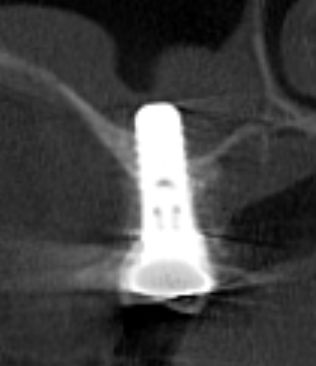

●最終的な歯の形を考えて、それに合わせて治療がすすめられる(理想的な位置に埋入できる)(トップダウントリートメント)

●歯ぐきを切開しなくてもインプラント手術が可能なケースがある

●下顎の場合、神経を回避してインプラント埋入ができる